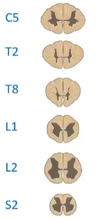

What is the spinal cord made up of?

Segments

How many nerves come out of each segment?

How are the segments named?

One from each side of the spinal cord (a pair of spinal nerves)

Corresponds to their position in the back / where it is on the spinal cord

What is the difference between the substances that make up the structures at 2 and 4?

Grey matter and white matter

What are the 2 projections (8 and 6) that go into and out of the grey matter?

What signals are conveyed through them?

Dorsal Root (posterior) - sensory / afferent

and Ventral Root (anterior) - motor / efferent

What are the smaller versions of the projections (5 and 7)?

The Dorsal and Ventral Rootlets

The grey matter in the spinal cord can be divided into which 2 parts (1 and 3)?

The Dorsal and Ventral Horns (posterior and anterior respectively)